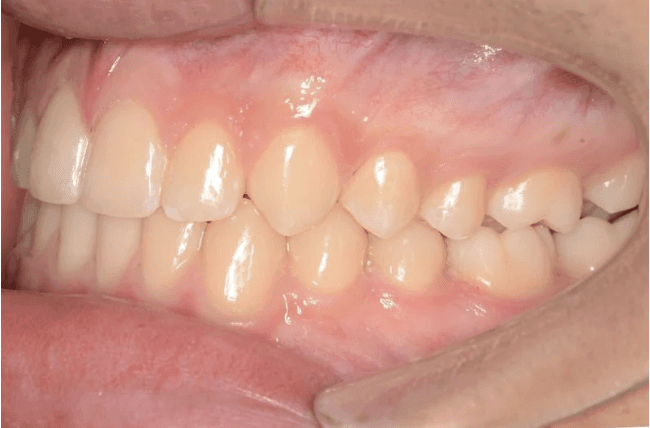

Initial treatment

INTRAORAL